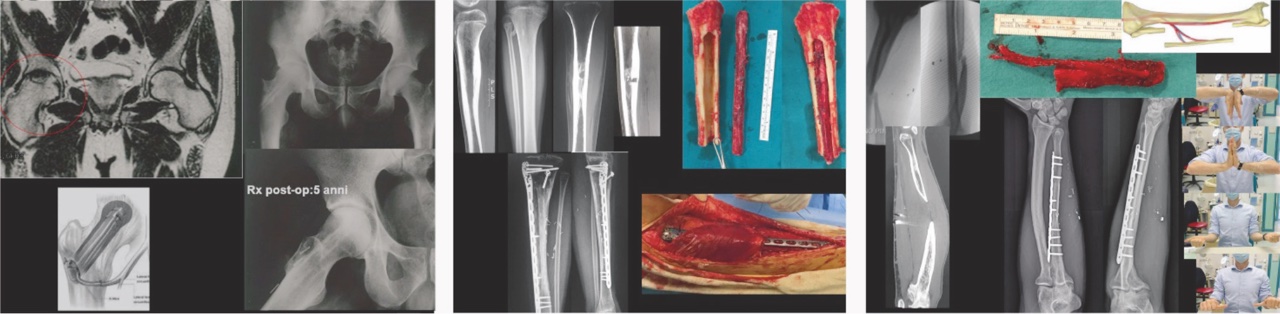

Cura di pseudoartrosi settiche e asettiche con difetti critici (Fig. 1b)

Ricostruzioni delle dita della mano con trasferimenti digitali dal piede (Fig. 1c)

Rivascolarizzazione in caso di osteonecrosi: tipica la testa femorale (Fig. 2a) e il semilunare del polso

Ricostruzioni ossee complesse (post traumatiche o in seguito a resezioni oncologiche) (Fig. 2b)

Lembi liberi ossei

La loro introduzione nella pratica clinica ha rivoluzionato il trattamento delle grandi perdite di sostanza ossea. Il perone vascolarizzato, il condilo femorale mediale e la cresta iliaca sono gli autotrapianti ossei più utilizzati. Il perone è senza dubbio il più versatile e si presta alla ricostruzione di segmenti diafisari di ossa lunghe. In caso di perdite di sostanza di ossa di maggior diametro, come la tibia e il femore, può essere associato a innesti massivi da donatore secondo la tecnica descritta dal Prof Capanna e dalla scuola di del Prof Campanacci 3 (Fig 2b). È molto utile nei soggetti in accrescimento il prelievo con l’epifisi prossimale del perone in quanto può crescere assieme al paziente.

Trattandosi di un tessuto vivente è in grado di consolidare secondo tempi fisiologici, di riparare le fratture e di rispondere all’eventuale incremento delle sollecitazioni meccaniche ipertrofizzandosi. Inoltre, l’osso vascolarizzato offre elevate garanzie di successo anche in circostanze particolarmente difficili comenel caso di distretti riceventi irradiati o infetti (Fig. 2c).

Esistono poi una serie di lembi che si chiamano compositi cioè che uniscono sullo stesso peduncolo più tessuti: sono un esempio il gran dorsale con la cute e/o con una costa, il serrato con la costa, la scapola con il gran dorsale, il perone con una paletta cutanea ed eventualmente una parte del soleo e così via. Questi lembi compositi possono risolvere problemi e difetti osteocutanei complessi con un solo intervento chirurgico. Anche le dita del piede devono essere considerate dei lembi compositi, e possono essere impiegate e trasferite per ricostruire le dita della mano o la polpa delle dita permettendo un ripristino della funzione e della sensibilità pressochè complete (Fig. 1c).